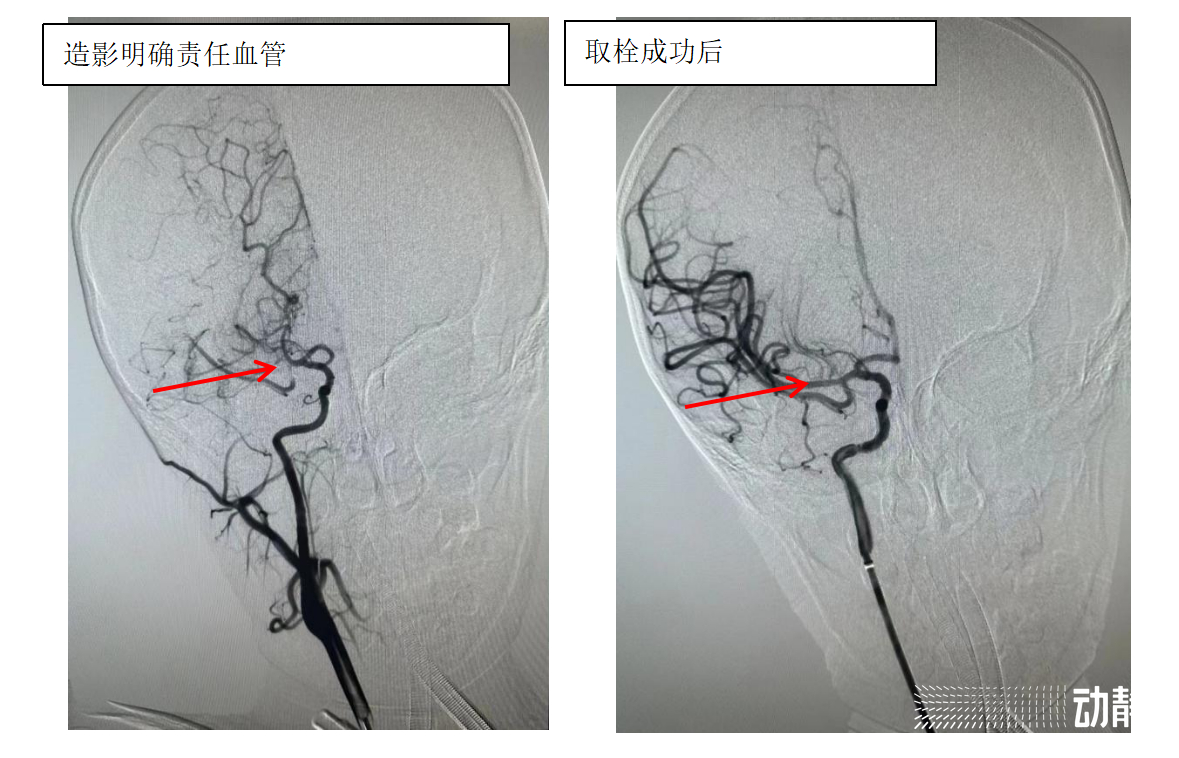

在麻醉科、小儿重症医学科等专业人员床旁监护下,介入团队成功在患儿脑组织窗内进行介入手术,成功取出患儿“肇事血栓”,右侧大脑中动脉前向血流恢复,为患儿疏通了“生命河流”。术后,瀛瀛在儿科重症医师的精心治疗下,逐渐恢复正常,目前已经顺利出院。